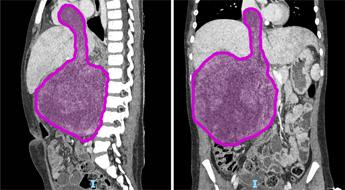

“Sara (nome di fantasia), 8 anni appena compiuti, era affetta da un nefroblastoma al rene destro che si estendeva all’interno della vena renale, della vena cava inferiore fino a raggiungere l’atrio destro del cuore, a causa di una trombosi neoplastica. Questa rara estensione del tumore – ha spiegato l’ospedale – si verifica in appena il 4-10% dei casi di nefroblastoma. Prima dell’intervento Sara è stata sottoposta a sei cicli di chemioterapia, eseguiti dal team di oncologi guidati dal professor Franco Locatelli, per ridurre la massa tumorale e facilitare l’operazione.

La fase preparatoria pre-chirurgica si è avvalsa di tecniche all’avanguardia di diagnostica per immagini come l’elaborazione 3D del tumore da asportare realizzata dall’unità di Imaging avanzato cardiotoracovascolare e fetale”.